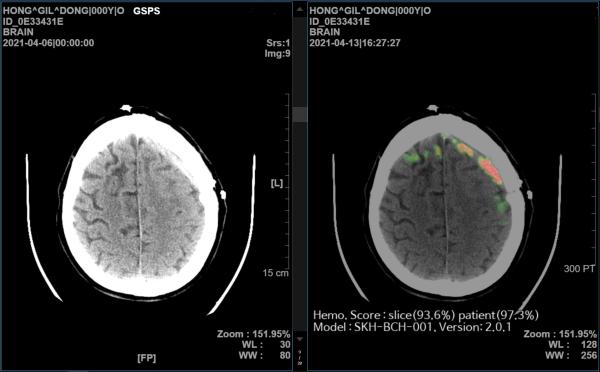

SK씨엔씨는 2019년부터 서울대 및 아주대학교병원과 협력해 AI 기반 뇌출혈 영상 의료 솔루션을 개발했다. 이 솔루션은 뇌 CT영상을 수초 내로 분석해 98% 이상 정확도로 출혈 위치와 이상 여부를 의료진에게 바로 알려준다.